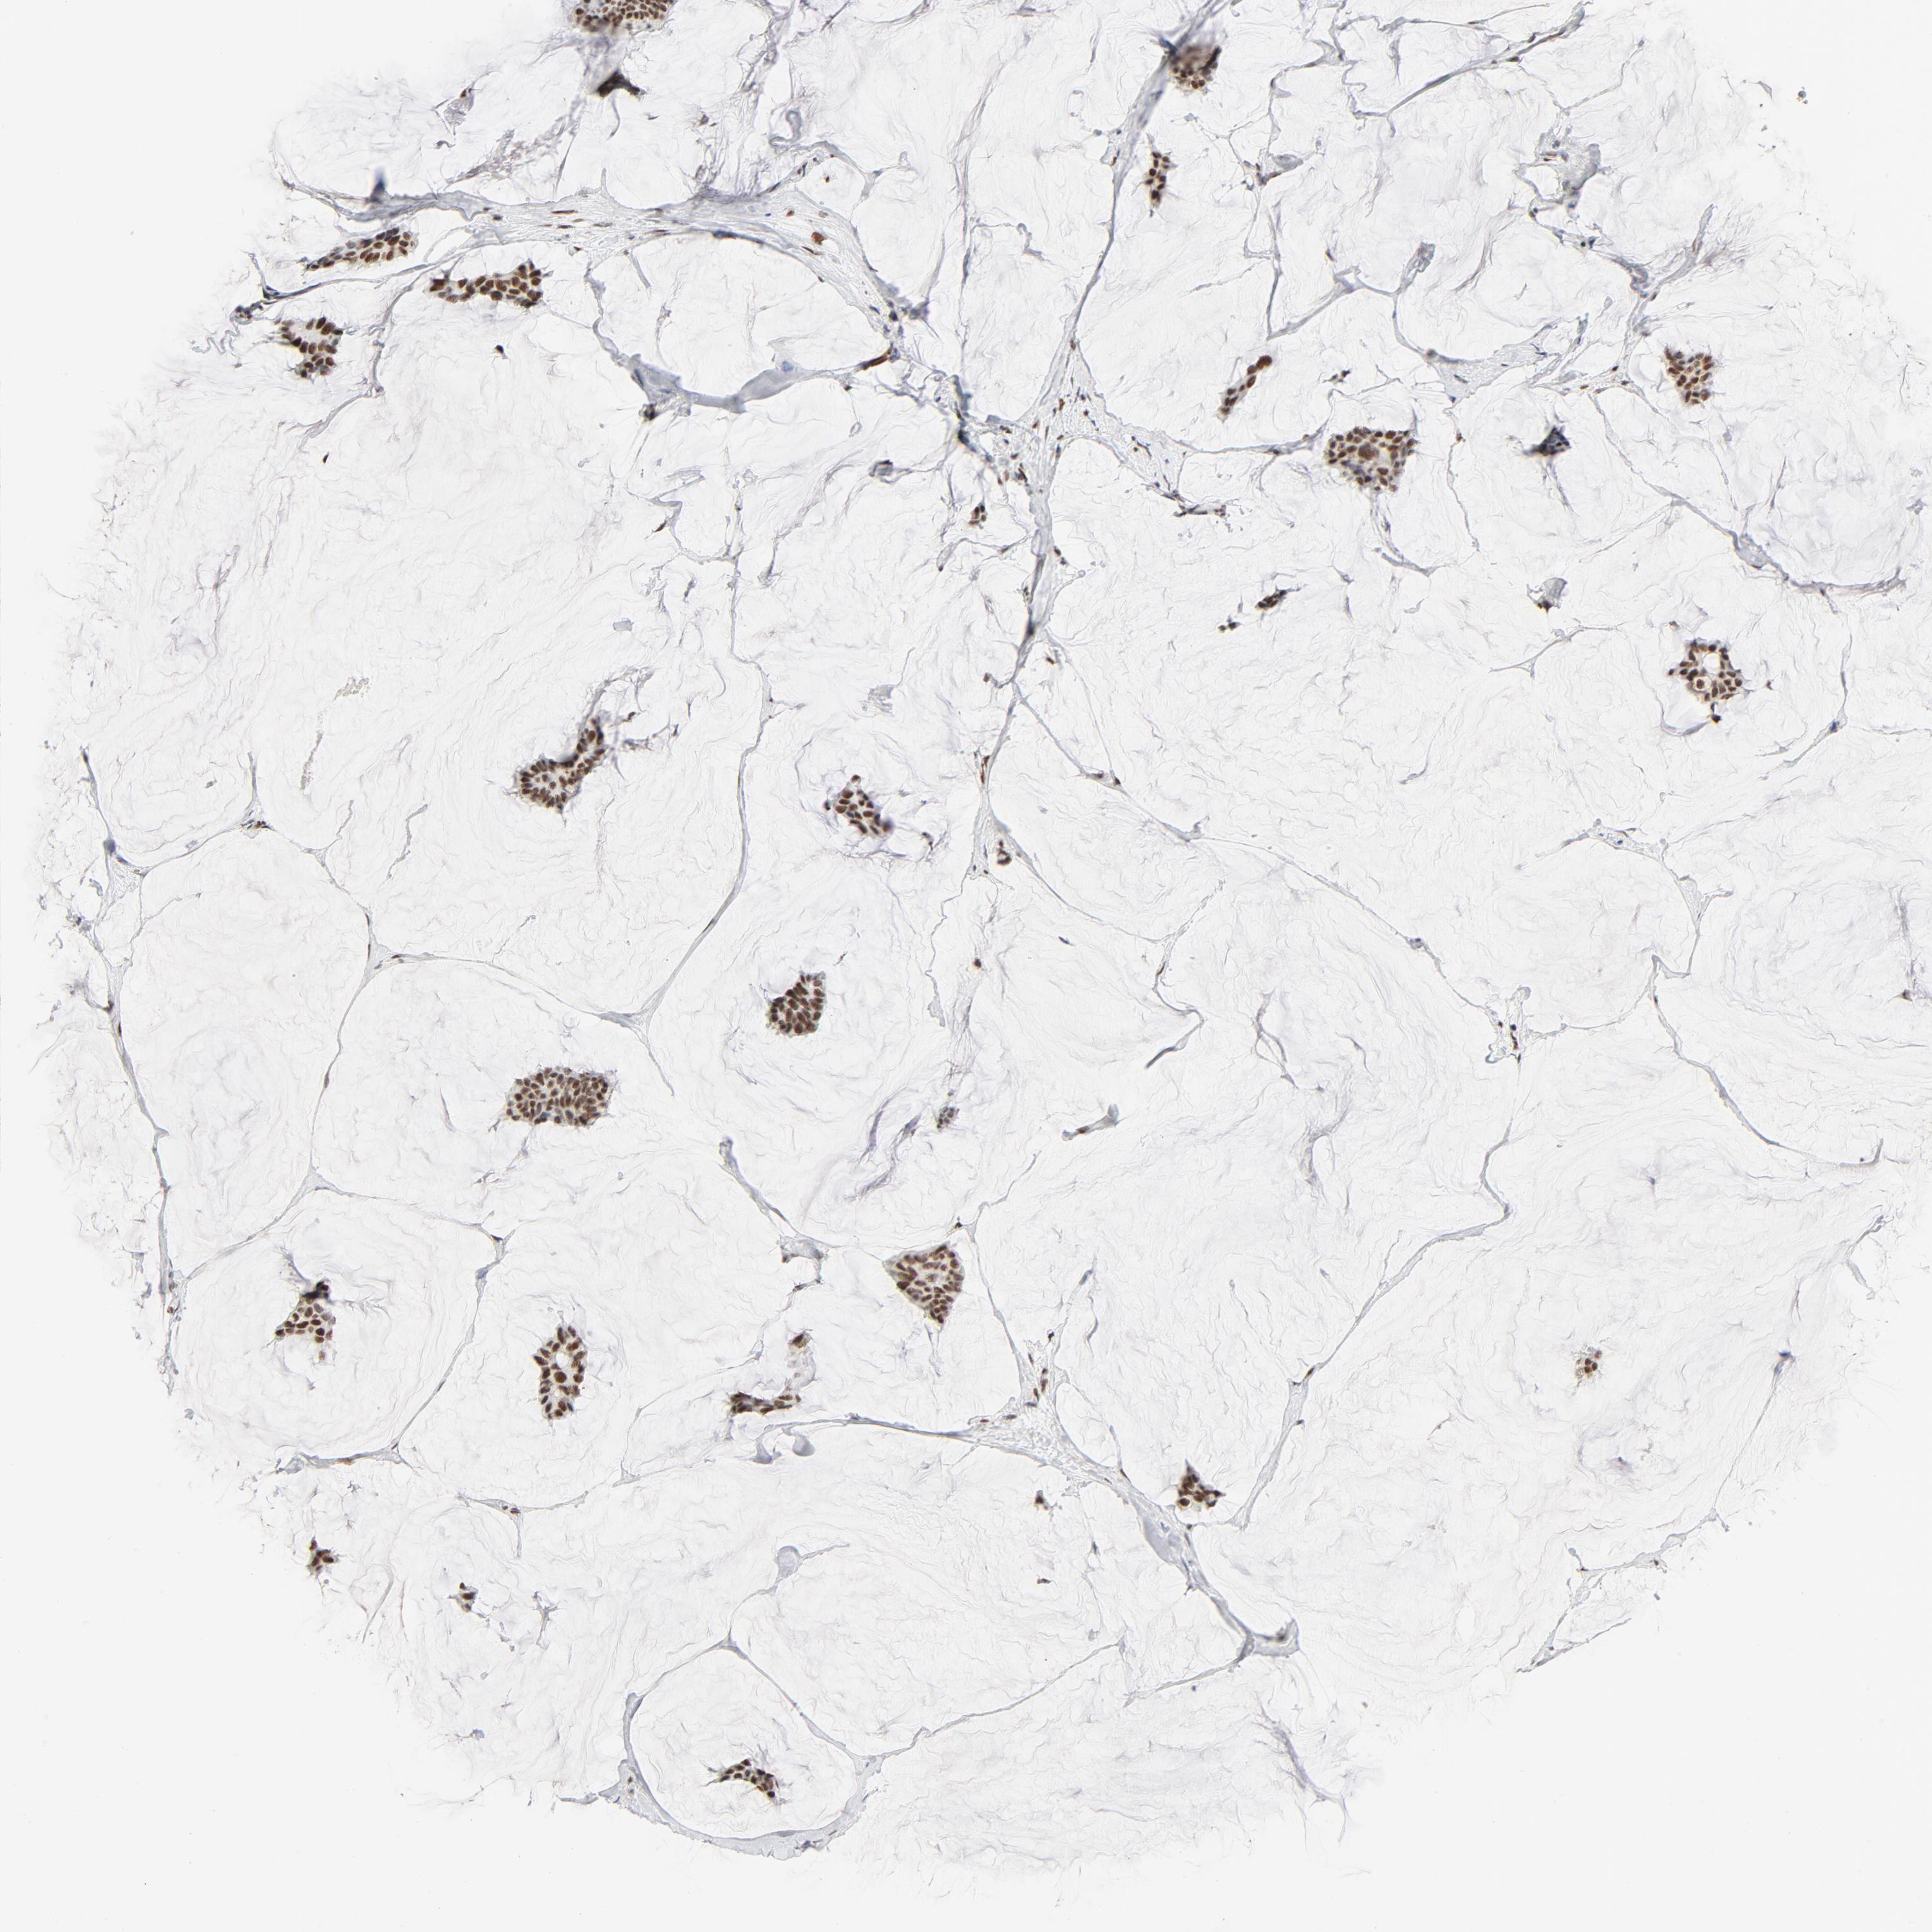

CANCER BREAST CANCER Show tissue menu

BRCA TCGA BRCA VALIDATION PROTEIN EXPRESSION